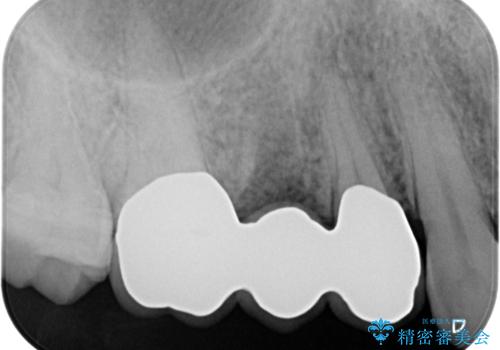

抜歯を行い、咬合機能の回復を行いますが、咬合関係や非常に強い噛み合わせの問題をふまえ、咬合面をメタルにしたメタルボンドブリッジで治療を行うこととしました。

また噛み合わせが深くブリッジの強度が十分に確保できないことから、抜歯時に歯周外科を行うことで十分に安定したクラウン装着をできるような処置を行っています。

術前・術後でブリッジ治療をした部分の歯肉ラインを整えたことで安定したブリッジを製作することができました。